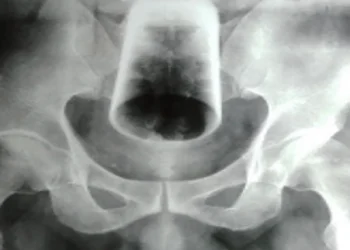

Man, 47, undergoes surgery after inserting water glass in his rectum, leaving it there for 3 days

Man, 47, undergoes surgery after inserting water glass in his rectum, leaving it there for 3 days A 47-year-old man ...